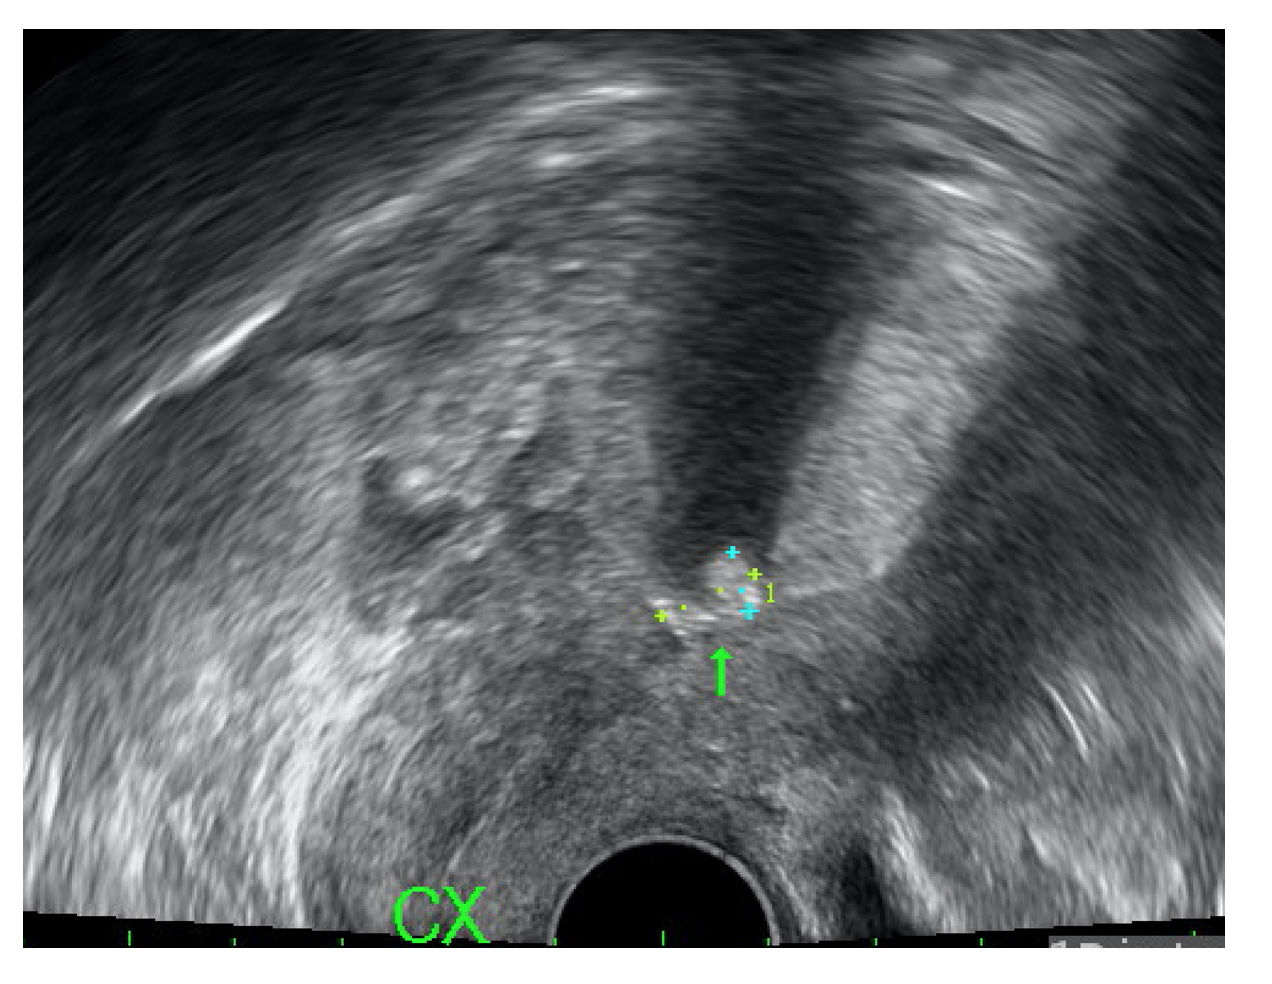

The second patient, a 35-year-old woman (gravida 3, para 2), presented with abdominal pain in the left lower quadrant for one month. She was previously treated at a regional hospital six weeks ago with laparoscopic surgery and hysteroscopic polypectomy for a tubo-ovarian abscess and an endometrial polyp, respectively. She had evidence of cervical motion tenderness and mildly elevated C-reactive protein levels (7.44 mg/L). Ultrasound revealed an irregular hyperechoic avascular lesion (size: 0.96 cm) located at the isthmus (Fig. 3). Office hysteroscopy identified the presence of a piece of crumpled plastic wrap (Fig. 4). Histologically, the proliferative-phase endometrium shows scattered plasma cells and neutrophils in the stroma and infiltration of neutrophils into the surface epithelium. Acute and chronic endometritis caused by a previously positioned membranous AAB was confirmed. Metronidazole 500 mg every 12 hours for 3 days was prescribed and she had no specific urogenital complaints for the next 12 months.

Fig. 3.Ultrasound revealed an irregular hyperechoic avascular lesion (size: 0.96 cm) located at the isthmus.